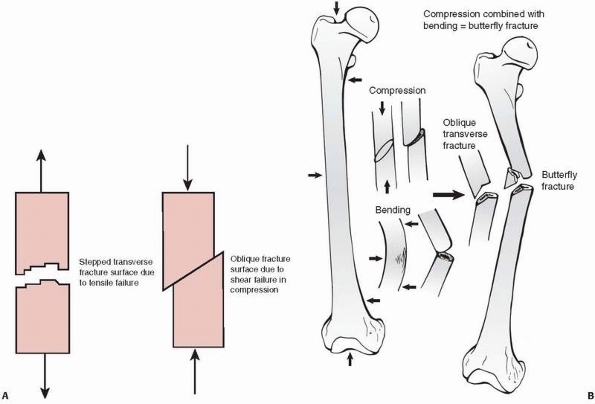

by shear, indicated by slippage along the diagonal, because bone is

weaker in shear than in compression (Fig. 1-24).

diaphysis caused by pure compressive forces. The butterfly fracture (Fig. 1-24)

results from combined bending and compression. Bending load causes the

fracture to start to fail in tension producing a transverse crack, but

as the crack progresses and the remaining intact bone weakens, it

starts to fail in compression, causing an oblique (shear) fracture

line. As the ends of the failing bone are driven together, a third

fragment—the butterfly—may result as the

oblique

fragment splits off. The production of a butterfly fragment probably

depends on the timing and magnitude of the two basic applied loads:

compression and bending.

FIGURE 1-24 A. Left:

Tensile fracture causes a stepped surface as fibers pull apart. The crack progresses, then steps to an adjacent region in which failure continues. Right: Pure compression of cortical bone results in failure by shearing or sliding along oblique surfaces. In reality, pure compression of a long bone (in a fall for example) results in crushing of the much weaker metaphyseal trabecular bone with a pilon fracture of the distal tibia or a tibial plateau fracture as the result. B. Some fractures that combine bending and compression demonstrate transverse cracking as a result of bending followed by an oblique crack characteristic of compressive failure. The butterfly fracture with additional splitting of the fragment secondary to the initial fracture is an example. |